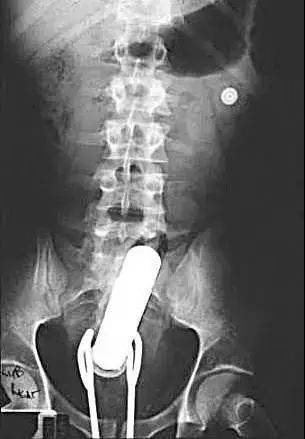

不要盲目自救......X光*体下**内的按摩棒……和一把沙拉钳。|medscape.com